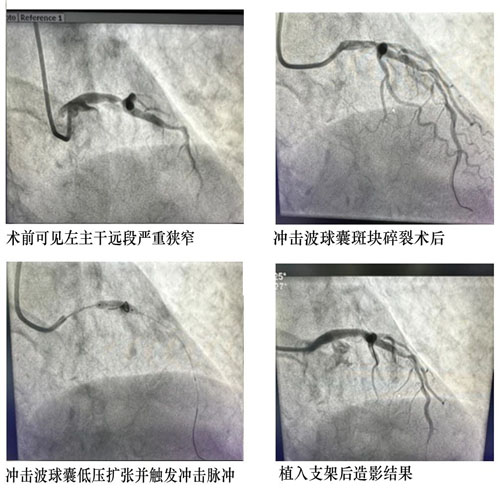

患者,男,80歲,1個月前因胸痛收住院。冠脈造影提示左主干至前降支鈣化病變導致80-90%狹窄,右冠脈閉塞。患者冠脈病變嚴重,手術風險較高,先期開通閉塞右冠病變并植入支架治療,此次處理左主干病變。

患者年齡大,左主干重度狹窄并嚴重鈣化,常規PTCA(經皮冠狀動脈腔內血管成形術)難以充分處理病變,可能導致支架無法順利通過、膨脹不全等風險。心血管內科CCU討論后決定應用沖擊波球囊,選擇3.5×12mm Shockwave球囊精確定位于LM-LAD鈣化病變嚴重處,根據標準操作流程,4ATM低壓力擴張球囊,累計觸發2個周期的沖擊波鈣化斑塊碎裂術,利用聲波壓力震碎血管壁內鈣化沉積,解決了嚴重鈣化病變普通球囊無法充分擴張的難題,復查冠脈造影見鈣化病變狹窄明顯減輕。經1小時手術治療,成功植入藥物支架1枚,解除血管狹窄,患者未再有癥狀,順利出院。